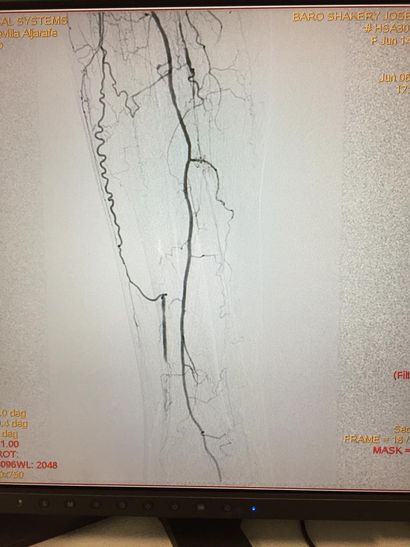

En casos en los que la neuropatía e infección se asocian con isquemia o falta de circulación arterial de la pierna, es necesario una valoración por Cirugía Vascular

para intentar buscar la revascularización mediante by pass o dilataciones endovasculares.